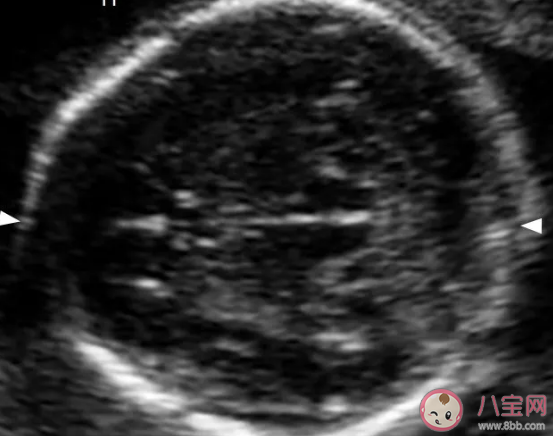

在檢查中胎兒心臟部位有強(qiáng)光點(diǎn)基本上時(shí)沒有什么問題的,超聲印象顯示的是超聲表現(xiàn),并不是說(shuō)胎兒一定患有心臟問題,只要孕媽之前做了唐篩基本上是不會(huì)出現(xiàn)預(yù)料之外的事情,孕媽實(shí)在擔(dān)心的話也可以進(jìn)行無(wú)創(chuàng)DNA的檢查,只要該檢查是沒有問題的,那么胎兒心臟處出現(xiàn)的“強(qiáng)光點(diǎn)”絕對(duì)不會(huì)有任何的問題,因?yàn)樗木S是對(duì)寶寶整體的一個(gè)大排畸,所以孕媽們一定要在準(zhǔn)確的時(shí)間點(diǎn)去進(jìn)行檢查,如果超過四維的檢查時(shí)間是沒有辦法在進(jìn)行大排畸的。

“心臟強(qiáng)光點(diǎn)”是四維檢查經(jīng)常出現(xiàn)的一種現(xiàn)象,該強(qiáng)光點(diǎn)雖然有可能是“病理性”的。但是絕大部分的胎兒并不會(huì)受其影響,隨著時(shí)間的變化,這些強(qiáng)光點(diǎn)也會(huì)慢慢的消失不見,孕媽需要冷靜的去對(duì)待

我們知道胎兒在發(fā)育是時(shí)身體的器官發(fā)育的速度有快有慢,這就會(huì)導(dǎo)致一部分機(jī)能出現(xiàn)“鈣化”,特別是心臟部位這種“鈣化”更是常見,當(dāng)寶寶心臟出現(xiàn)該癥狀后反映在B超上就是出現(xiàn)“強(qiáng)光點(diǎn)”,這種強(qiáng)光點(diǎn)會(huì)隨著寶寶的不斷成長(zhǎng)發(fā)育被寶寶弱化和吸收掉,這種身體發(fā)育導(dǎo)致的“強(qiáng)光點(diǎn)”對(duì)胎兒身體并無(wú)影響,在孕周30后會(huì)逐漸的消失,孕媽可以安心無(wú)憂。

以積極的心態(tài)面對(duì)胎兒的各種問題固然是正確的,但是心臟強(qiáng)光點(diǎn)也有一定概率是寶寶心臟發(fā)育畸形,導(dǎo)致寶寶出現(xiàn)心臟異常常見的問題是由于染色體導(dǎo)致的,這種概率雖然有,但是概率非常低,其幾率為百分之一,所以孕媽遇到B超檢查發(fā)現(xiàn)胎兒心臟有強(qiáng)光點(diǎn)可暫時(shí)不處理,觀察一段時(shí)間以待確診,觀察期通常為30天左右,若強(qiáng)光點(diǎn)在四周后進(jìn)行檢查依舊存在,產(chǎn)科主治醫(yī)生會(huì)讓孕媽做一些檢查,如心臟彩超和無(wú)創(chuàng)DNA來(lái)進(jìn)行確診。

B超檢查出現(xiàn)“心臟強(qiáng)光點(diǎn)”的成因有很多,比如心臟強(qiáng)回聲,礦物沉淀或者乳頭的早期缺血性變化都會(huì)在孕媽檢查時(shí)在B超印象上顯示該部位出現(xiàn)強(qiáng)光點(diǎn),在心臟的逐漸發(fā)育和孕期的增加,絕大部分都會(huì)隨著時(shí)間的推移慢慢消失。

強(qiáng)光的表現(xiàn)也表示胎兒有可能有NT增寬、腎盂分離、腸道強(qiáng)回聲、四肢長(zhǎng)骨短、鼻骨短小等臨床表現(xiàn)。如果寶寶強(qiáng)回聲光點(diǎn)只出現(xiàn)在左心室,而且只有一枚,那么孕媽可以放心。這是沒有什么臨床意義,但是如果右心室也有的話,那么就需要進(jìn)行下一步檢查。

通常強(qiáng)光點(diǎn)隨孕周增加而縮小,到37周的時(shí)候就已經(jīng)完全消失,但是也有一部分一直存在,如果說(shuō)單純光點(diǎn)5mm,這種情況是因?yàn)殁}化現(xiàn)象,99%是沒事的。